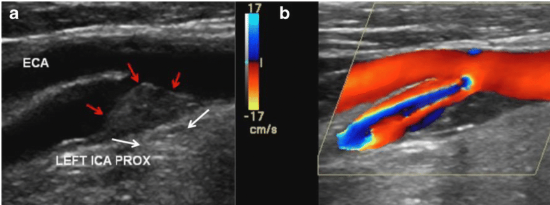

Review ultrasound image and answer following questions:

1. The red arrows indicate what on grayscale?

2. How would you describe surface? How would you describe echogenicity?

3. Color is activated with image 'B', what is term used to describe color patterns center of blood flow? Why is this happening?

4. At which locations will you sample blood flow to determine velocities with this finding? Why will we sample blood flow in these locations?

Plaque

Smooth. Heterogenous

aliasing because the velocities are exceeding the Nyquist limit

Walk sample through stenosis and find the highest velocity. Then grab the prox, distal, and the slow return to laminar.